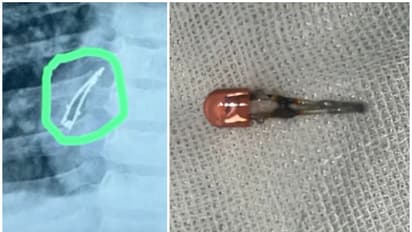

അഹമ്മദാബാദ്: ഒമ്പത് മാസം പ്രായമുള്ള ഒരു കുഞ്ഞ് അബദ്ധത്തിൽ വിഴുങ്ങിയ എൽഇഡി ബൾബ് പുറത്തെടുത്തു. ഗുജറാത്തിലെ അഹമ്മദാബാദിലാണ് സംഭവം. കളിപ്പാട്ട ഫോണിൽ ഉണ്ടായിരുന്ന എൽഇഡി ബൾബ് ആണ് കുഞ്ഞ് വിഴുങ്ങിയത്. രണ്ടാഴ്ച തുടർച്ചയായി ചുമ മാറാത്തത് കൊണ്ടാണ് മുഹമ്മദ് എന്ന് പേരുള്ള കുട്ടിയെ അഹമ്മദാബാദ് സിവിൽ ആശുപത്രിയിൽ പ്രവേശിപ്പിച്ചത്.

കുട്ടിയുടെ മാതാപിതാക്കൾ ആദ്യം ജുനാഗഡിലെ ഒരു ശിശുരോഗ വിദഗ്ദ്ധനെയാണ് കാണിച്ചത്. അദ്ദേഹം തുടർ ചികിത്സയ്ക്കായി ആശുപത്രിയിലേക്ക് റഫർ ചെയ്യുകയായിരുന്നു. ആശുപത്രിയിലെ മെഡിക്കൽ പ്രൊഫഷണലുകൾ ബ്രോങ്കോസ്കോപ്പി നടത്തി മുഹമ്മദിന്റെ ശ്വാസനാളത്തിൽ നിന്ന് ബൾബ് നീക്കം ചെയ്തു. കുട്ടി ഇപ്പോൾ സുഖമായിരിക്കുന്നുവെന്നും ഉടൻ ആശുപത്രി വിടുമെന്നും മെഡിക്കൽ സംഘം സ്ഥിരീകരിച്ചു.

കുട്ടികളിൽ അസാധാരണമായ ലക്ഷണങ്ങൾ കാണിക്കുമ്പോൾ, പ്രത്യേകിച്ച് എന്തെങ്കിലും വിഴുങ്ങിയത് സംശയം തോന്നിയാല് ഉടനടി വൈദ്യസഹായം തേടണമെന്ന് ഡോക്ടര്മാര് പറഞ്ഞു. മുഹമ്മദ് കളിപ്പാട്ട ഫോൺ ഉപയോഗിച്ച് കളിക്കുമ്പോളാണ് സംഭവം നടന്നതെന്ന് മാതാപിതാക്കൾ പറഞ്ഞു. എൽഇഡി ബൾബ് വേർപെട്ട് അബദ്ധത്തിൽ ഇത് വിഴുങ്ങുകയായിരുന്നു. ഇത് ചുമയ്ക്കും അസ്വസ്ഥതകൾക്കും കാരണമാവുകയായിരുന്നു.